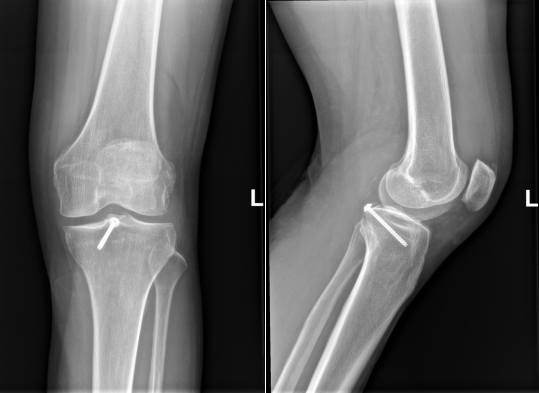

▲术后X片提示膝关节交叉韧带止点撕脱骨折

已复位、固定